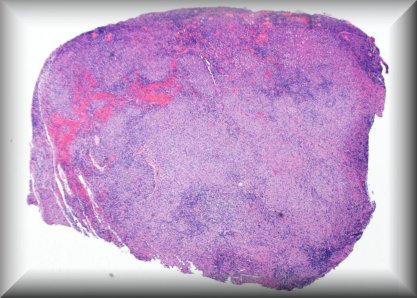

Josef Sach (Prague): Orbital sarcoidosis. |

![]() |